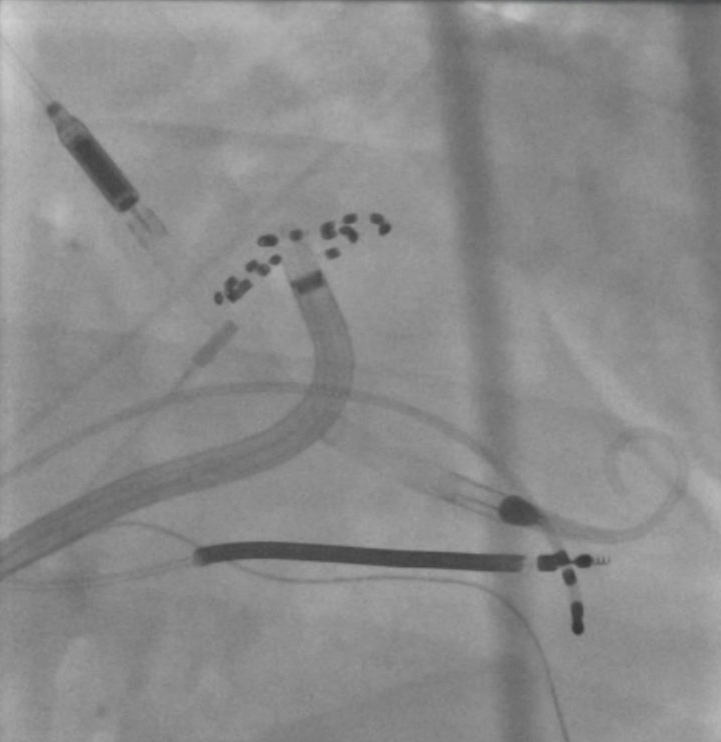

Unfortunate 33 y/o transferred for AE Fistula 6 years ago had thoracotomy, mediastinal debridement, esophageal stenting/removal. 6 yrs later presented with microreentrant flutter from the scar related to the AE infection. #Epeeps @gautamsand @narrowQRS @jskoruth @EJSMD @SergioPinski

Madhu Reddy tweet mediaMadhu Reddy tweet media